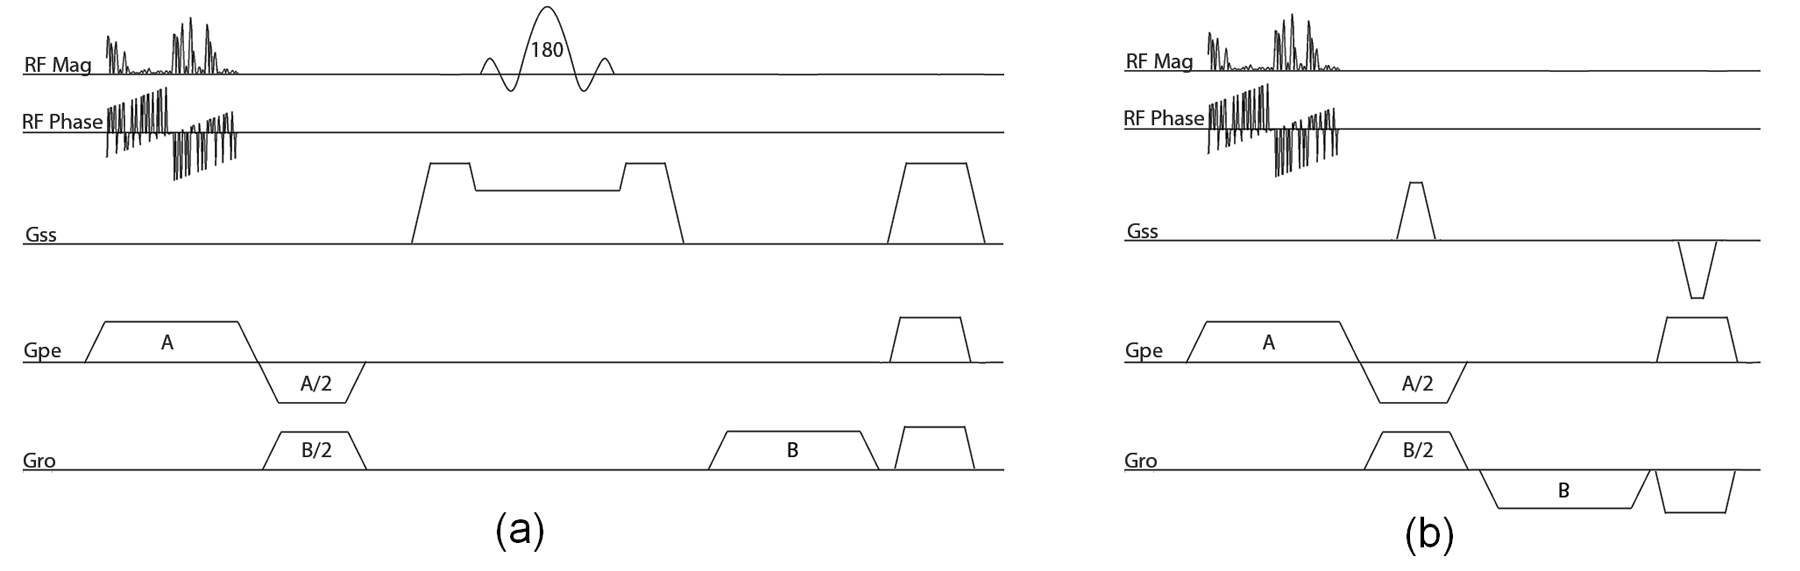

3.3 Pulse Sequence Design for Noiselet Encoding

In conventional 2D MR imaging sequences, a spatially selective RF excitation pulse is used to select the slice and the linear spatial gradients are used to encode the excited slice onto the Fourier transform space. In [42, 43, 31, 32], it is demonstrated that the spatially selective RF excitation pulse can also be used to encode the imaging volume. In [44, 32, 45, 25], the wavelet, SVD and random encoding profiles have been implemented using the spatially selective RF excitation pulses. An analysis using the linear response model described in [42] provides a theoretical framework to design spatially selective RF excitation pulses for implementation of non-Fourier encoding. Under the small flip angle ( 30∘) regime, the RF pulse envelope can be calculated directly by taking the Fourier transform of the desired excitation profile. However this method of designing an RF excitation pulse requires excellent RF and main field homogeneity.

To excite a noiselet profile during excitation, one can design an RF pulse envelope by directly taking the Fourier transform of the noiselet basis functions. For an image of size 256256, the noiselet measurement matrix has 256 rows and 256 columns (see (12) for the low dimensional example). The Fourier transformation of each row of the noiselet matrix will result in 256 RF excitation pulses.

A pulse sequence for the noiselet encoding of 2D MR imaging is shown in Fig. 1 (a). The pulse sequence is designed by tailoring the spin echo sequence. The RF excitation pulse in the conventional spin echo sequence is replaced by the noiselet RF pulse, and the slice select gradient is shifted to phase encoding axis. The 180∘ refocusing RF pulse is used in conjunction with the slice selection gradient to select the slice that refocuses the spins only in the desired slice. Spoilers are used after the readout gradient to remove any residual signal in the transverse plane. A new RF excitation pulse is used for every new TR to excite a new noiselet profile, and a total of 256 TR are required for excitation of the complete set of noiselet bases. The readout gradient strength determines the FOV in the readout direction, while the phase encoding gradient strength and duration of the RF excitation pulse determines the field of view (FOV) in phase encoding direction. The FOV in phase encoding direction is determined as

| (13) |

where is the gradient strength in PE direction, is the gyromagnetic ratio, and is the dwell time of the RF pulse which is defined as = (Duration of RF pulse) / (Number of points in RF pulse). Equation (13) is used to calculate the gradient strength required in the phase encoding direction during execution of RF excitation pulse.

The method described above can also be used to design the pulse sequence for the noiselet encoding of 3D MR imaging as shown in Fig. 1 (b).